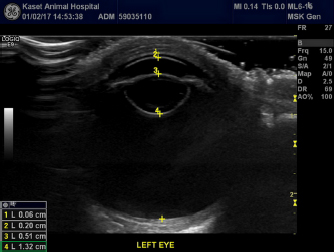

A 2-year-old intact female orangutan from an open zoo in Bangkok was presented with bilateral opacity of the lenses, showing slow movement and bumping into objects during 2 weeks of observation. Ophthalmic examination revealed complete cataract OU. Menace response was negative, whereas dazzle reflex and pupillary light reflex were positive OU. The conjunctiva, cornea, anterior chamber, and iris were evaluated as normal using a slit lamp biomicroscope (Kowa SL-17 Portable Slit-lamp biomicroscope, Kowa Co. Ltd, Tokyo, Japan). Intraocular pressures which were measured using a rebound tonometer (Icare®TonoVet, Icare Finland Oy, Helsinki, Finland) were normal (25 mmHg OU). Fundic examination could not be carried out due to cloudiness in the lenses OU. Definitive diagnosis was mature cataracts OU (Fig. 1). B-scan ocular ultrasonography (Logiq E9, GE Healthcare, WI) with topical 0.5% tetracaine hydrochloride (Alcon®, Alcon-Couvreur, Puurs, Belgium) revealed bilateral cataracts with no other ocular abnormalities (Fig. 2). Physical examination, hematology, and blood chemistry results were within normal limits. Cataract surgery with phacoemulsification and IOL implantation were planned. A-scan biometry was planned before the surgical date to prepare the IOL. Electroretinography was planned to be carried out just before phacoemulsification and dark adaptation was skipped to decrease the anesthetic period.

Fig. 2. B-scan ultrasonography revealing hyperechogenicity of lens capsule and cortex indicating cataract with normal other ocular structures for the left eye.